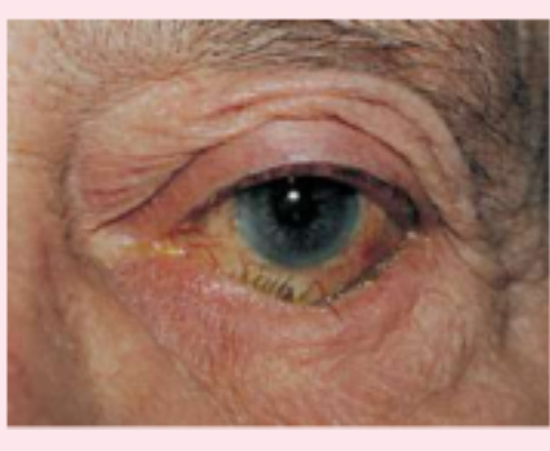

ectropion

outwardly turned lower lid